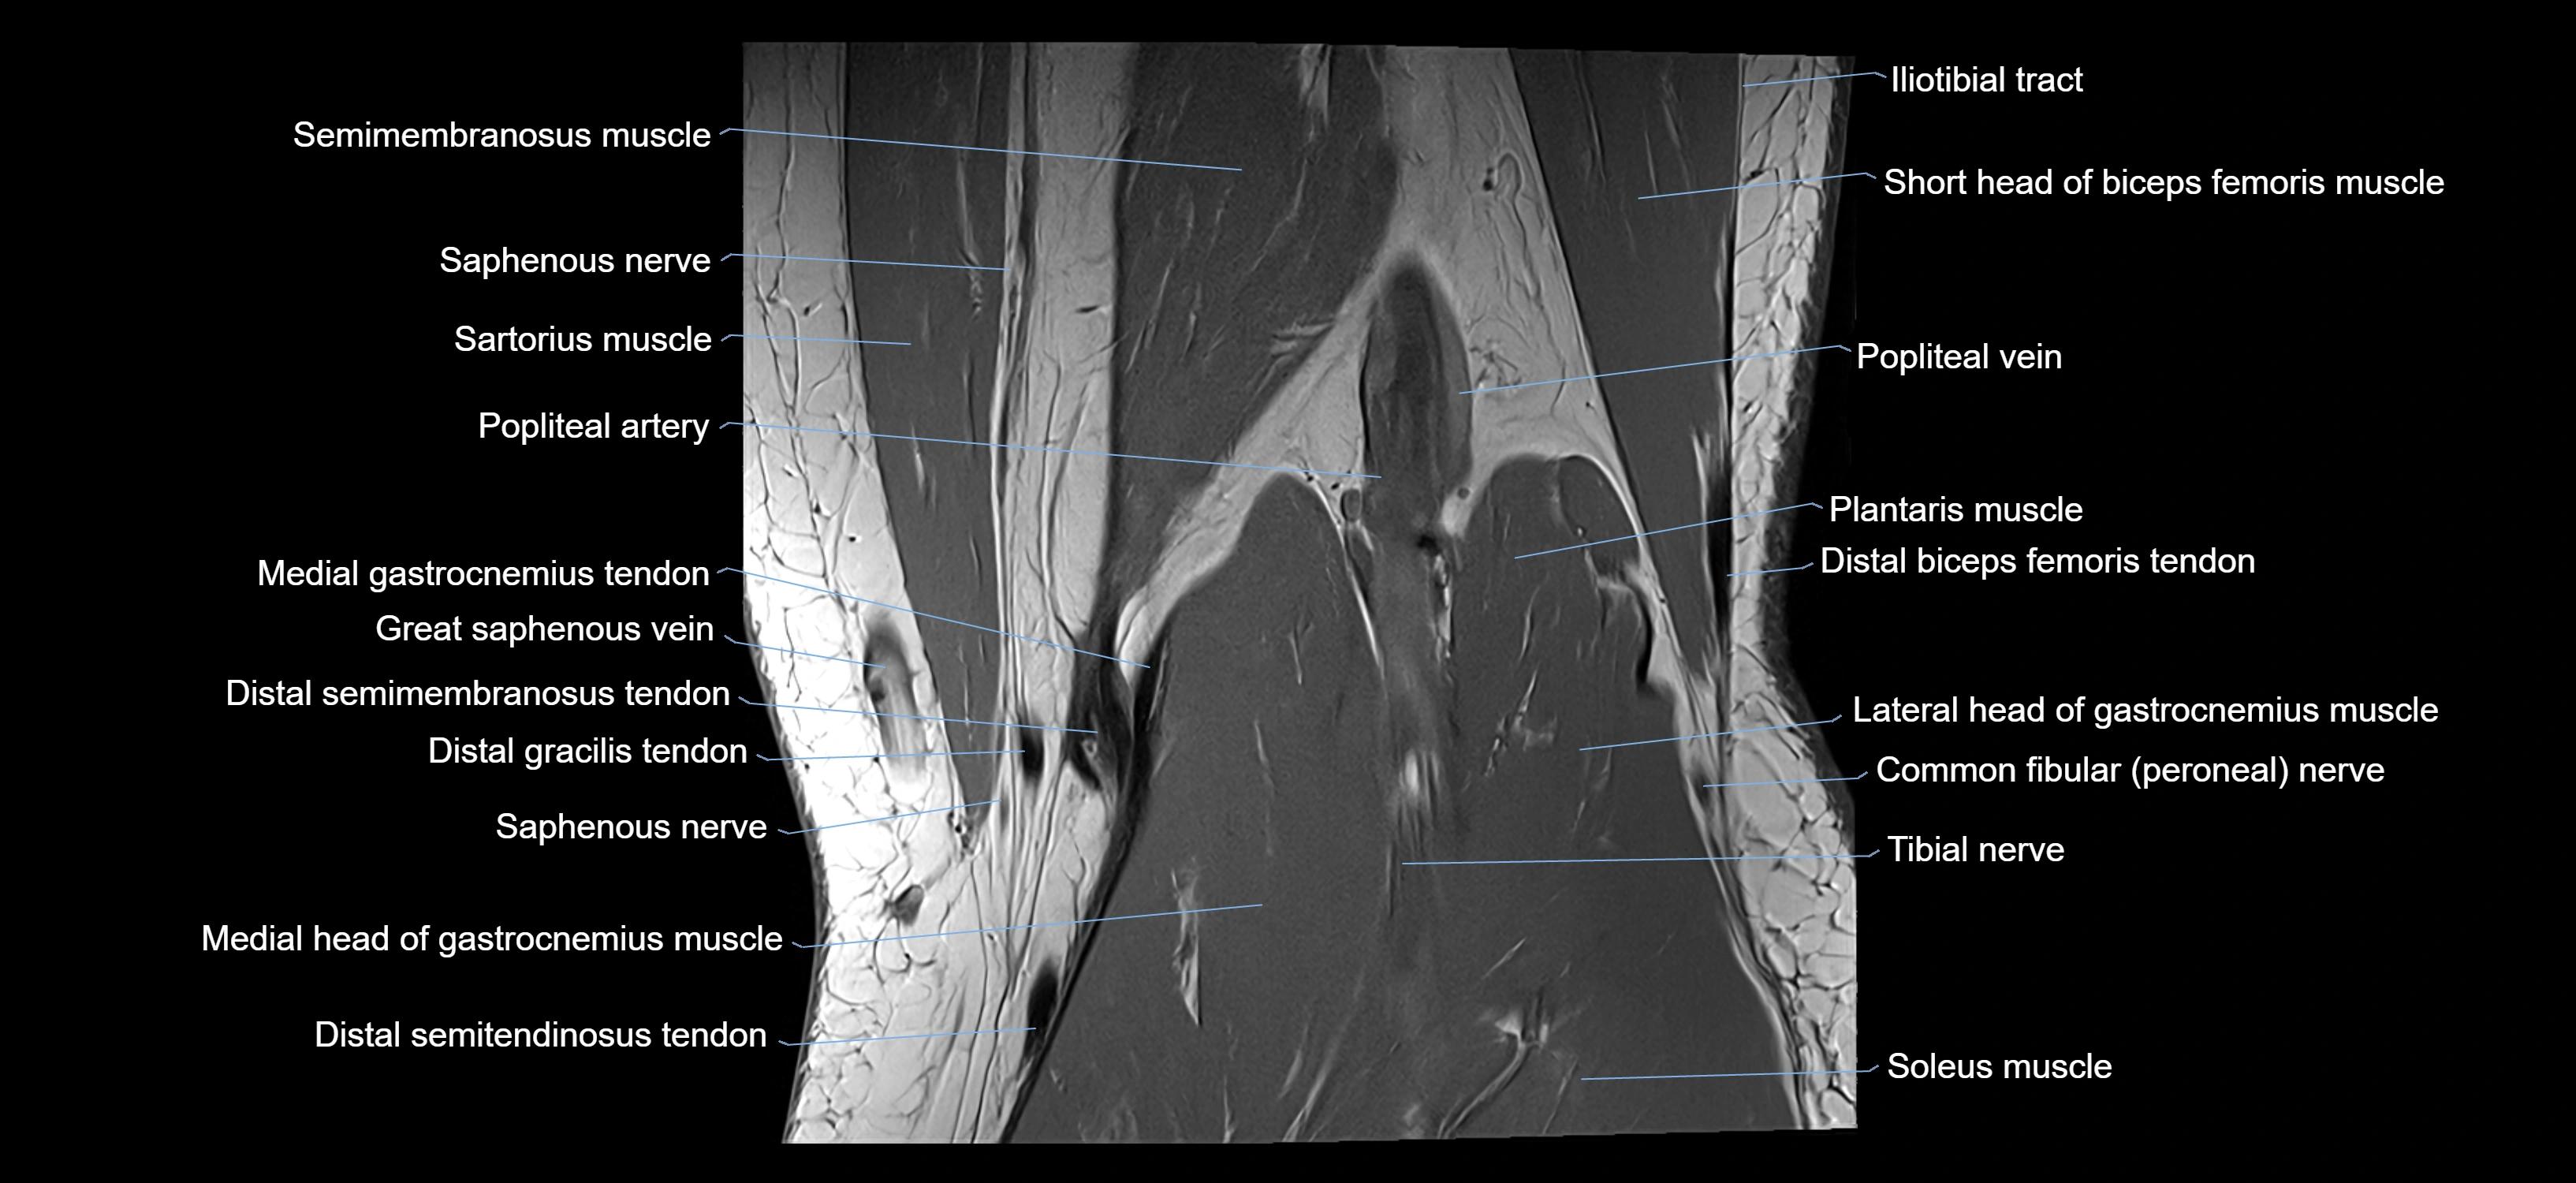

- Medial gastrocnemius tendon

- Medial head of gastrocnemius muscle

- Plantaris muscle

- Popliteal artery

- Popliteal vein

- Saphenous nerve

- Sartorius muscle

- Semimembranosus muscle

- Soleus muscle

- Tibial nerve